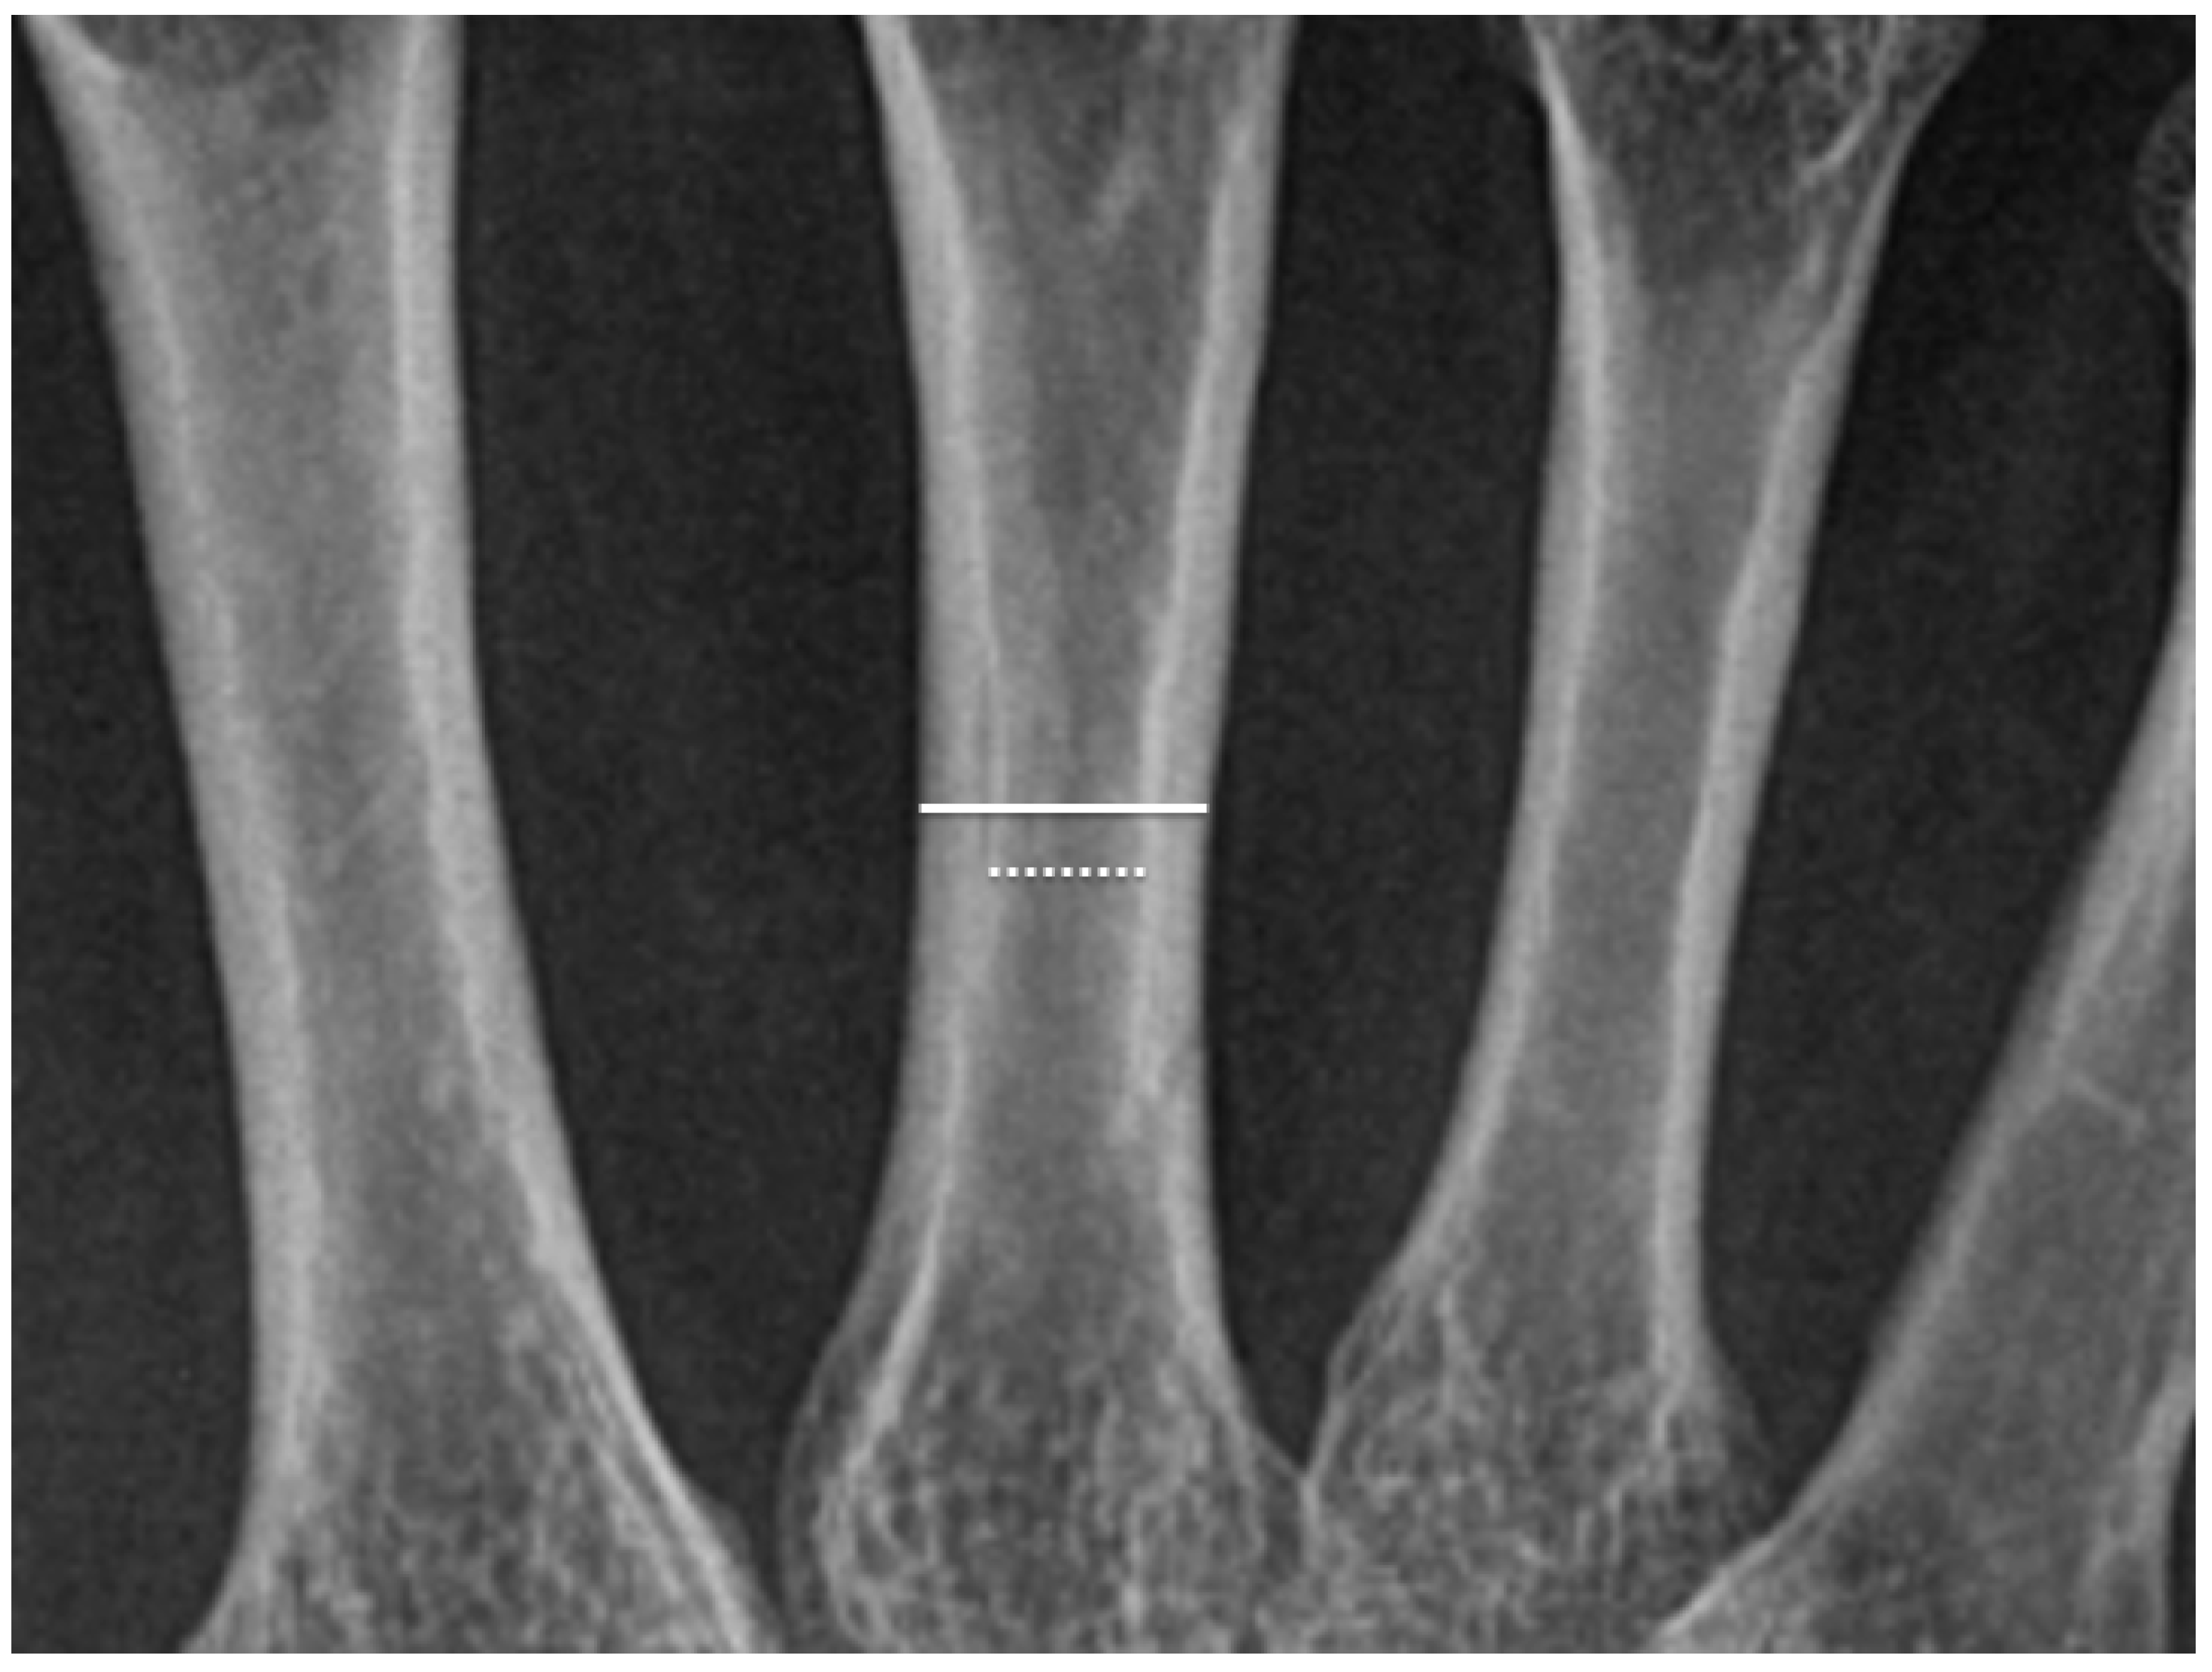

2.2. Methods

2.3. Radiological Examinations

3.2. Metacarpal CTR